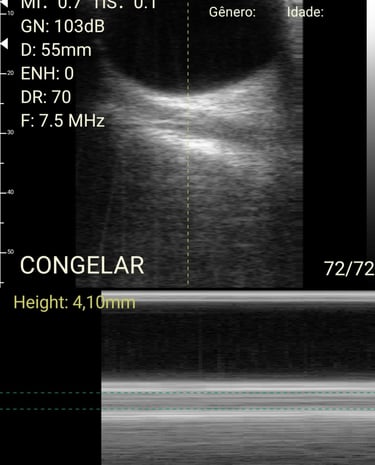

Análises detalhadas de procedimentos com o método HUGO.